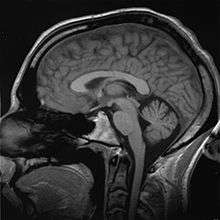

An MRI scan of a human head, an example of a biomedical engineering application of electrical engineering to diagnostic imaging. Click here to view an animated sequence of slices.

Imaging technologies are often essential to medical diagnosis, and are typically the most complex equipment found in a hospital including: fluoroscopy, magnetic resonance imaging (MRI), nuclear medicine, positron emission tomography (PET), PET-CT scans, projection radiography such as X-rays and CT scans, tomography, ultrasound, optical microscopy, and electron microscopy.